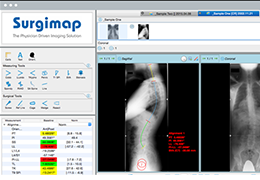

Talairach Tools

Talairach transformation is performed in two steps. The first step consists of rotating the 3D data set for each subject to be aligned with the stereotaxic axes. For this step the location of the anterior commissure (AC) and the posterior commissure (PC) as well as two rotation parameters for midsagittal alignment has to be specified interactively. In the second step the extreme points of the cerebrum are specified. These points together with the AC and PC coordinates are then used to scale the 3D data sets into the dimensions of the standard brain of the Talairach and Tournaux atlas.